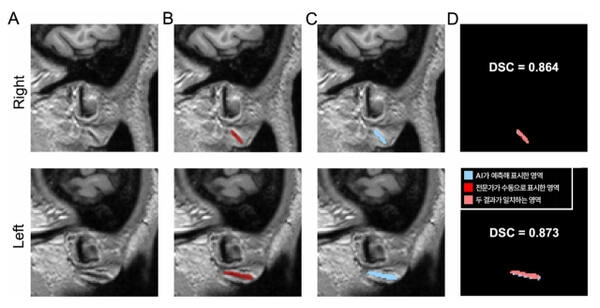

연구팀은 이러한 한계를 극복하기 위해 뇌 MRI를 찍을 때 뇌뿐 아니라 양쪽 귓불을 포함한 얼굴이 함께 촬영된다는 점에 주목했다. 뇌 MRI 영상에서 얼굴을 추출한 뒤, 귓불 부위를 분석해 프랭크 징후를 자동으로 찾아 표시하는 인공지능(AI) 모델을 개발했다.

연구팀은 분당서울대병원에서 수집한 400건의 뇌 MRI를 바탕으로 전문가가 수동으로 구분하고 표시한 프랭크 징후를 AI에게 학습시켰다. 이후 학습에 사용하지 않은 별도의 데이터셋(총 600건)으로 1차 검증, 충남대병원·강원대병원·세브란스병원 다기관 데이터셋(총 460건)으로 2차 검증을 진행했다.

그 결과 전문가가 수동으로 표시한 영역과 AI가 자동으로 분할한 영역의 일치 정도를 측정하는 DSC(Dice 유사도 계수, 1에 가까울수록 유사) 값이 두 차례의 검증에서 0.734, 0.714로 나타났다. 이는 AI가 찾아낸 영역이 전문가의 판단과 70% 이상 부합한다는 뜻으로, 의료영상 분야에서 높은 수준으로 인정받는다.